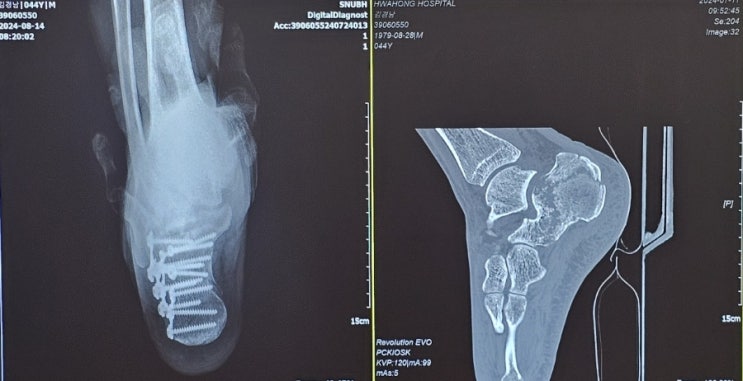

종골골절 후기 총정리 (수술후30일경과)사진 혐오주의

7월10일 떨어지면서 뒷꿈치 종골골절 처음에는 접지른줄알았는대 만지는순간 아~이건 무조건 부러졌다 생각...